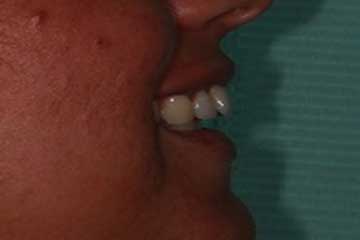

Trattamento ortodontico nell'adulto con intrusione del I° molare superiore mediante l'utilizzo di mini impianti